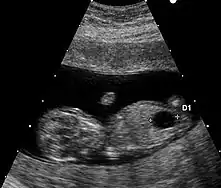

Le marqueur échographique utilisé est la clarté nucale. La technique de mesure doit répondre à des critères stricts.

Il existe un autre marqueur échographique mais de mesure plus délicate : l'os propre du nez.

Aucun signe échographique n'est symptomatique de la trisomie 21. Néanmoins, un certain nombre d'anomalies mineures ou majeures qui se rencontrent plus fréquemment dans cette maladie chromosomique peuvent être mis en évidence.

- Anomalies mineures

- hypoplasie ou absence des os propres du nez ;

- fémur court, inférieur au 5e centile pour l'âge ;

- épaisseur de nuque supérieure à 6 mm à 20 semaines ;

- écartement important entre les premier et deuxième orteils ;

- brièveté de la deuxième phalange du cinquième doigt (brachymésophalangie) ;

- langue protruse…